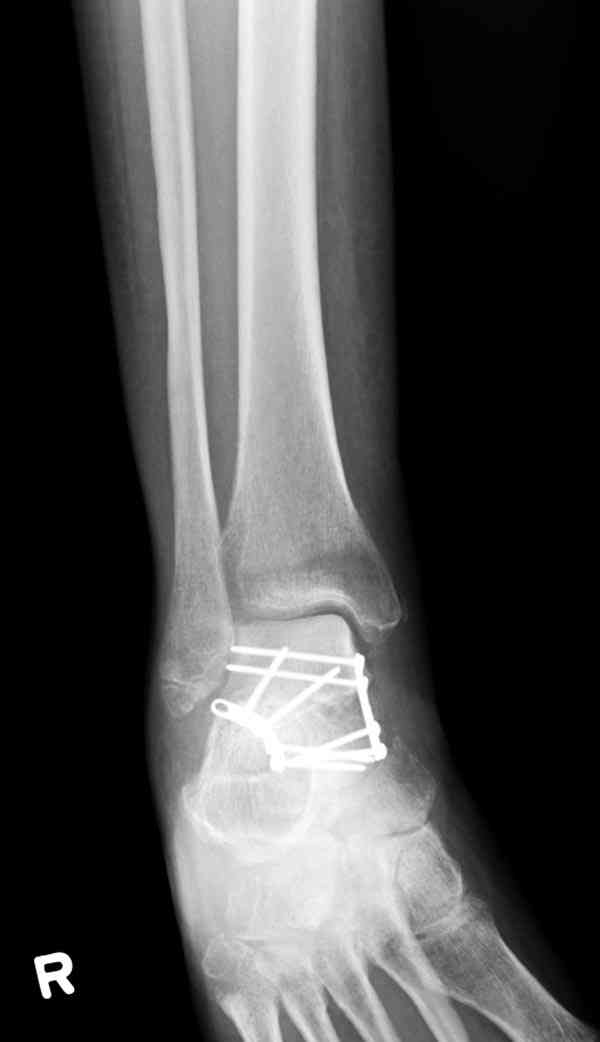

И второй случай из недавней ташкентской практики, (извините за качество ренгенограммы и только в одной проекции) случай падения с высоты (кстати моего друга - известного киноактера) - открытый

смещенный перелом тарана, с переломом переднего края дистального эпиметафиза большеберцовой кости.

При поступлении в приемной сделана первичная обработка с ушиванием открытой латеральной раны и вытяжением за пятку.

Из-за отсутствия времени пришлось оперировать на второе утро, из материала, что имеем на месте, фиксирован двумя шурупами, а третий-это контур сломанного жойстика в 4 мм. На дистальный медиальный конец тибиа antiglide 3.5 мм пластина. Через пару дней выписан и несмотря на предупреждение, самостоятельно начал нагрузку в 4 недели, время не ждет, снимается в боевике в Росийской Федерации.